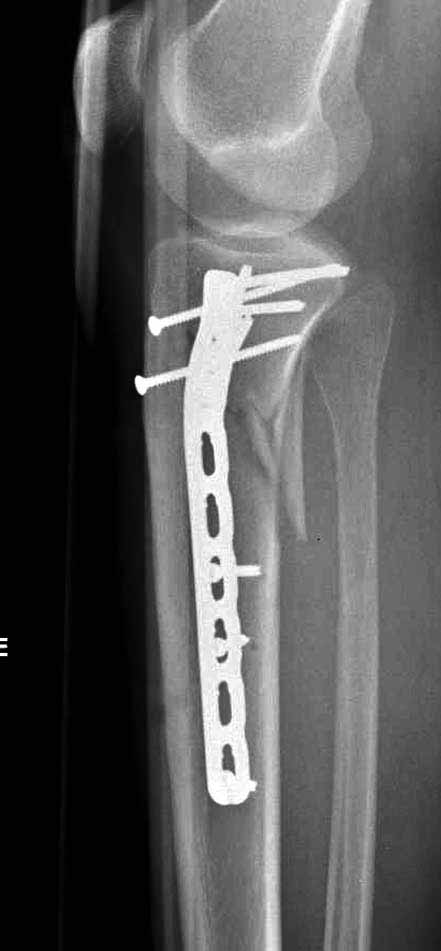

В приложении этапы фиксации Both Column Fx и пластиной Synthes для плеча при переломе медиального мыщелка.

Частая ошибка, когда фиксацию двух колонного перелома проводят одиночной пластиной, т.е с одной стороны, и такая фиксация не удерживает, происходит вторичноое смещение. Необходимо нейтрализовать второй пластиной или дополнительным наружным фиксатором.

Если у вас, кроме пластины, нет другого альтернативного варианта, тогда, учитывая мягкотканые проблемы с наружной стороны, я бы рекомендовал операцию делать в два этапа. Преимущества, сперва репозиция и фиксация перелома с медиальной стороны, а затем, после улучшения состояния мягких тканей, зафиксировать с латеральной стороны. Современные пластины имеют латеральный Jig для перкутанных мини доступов.